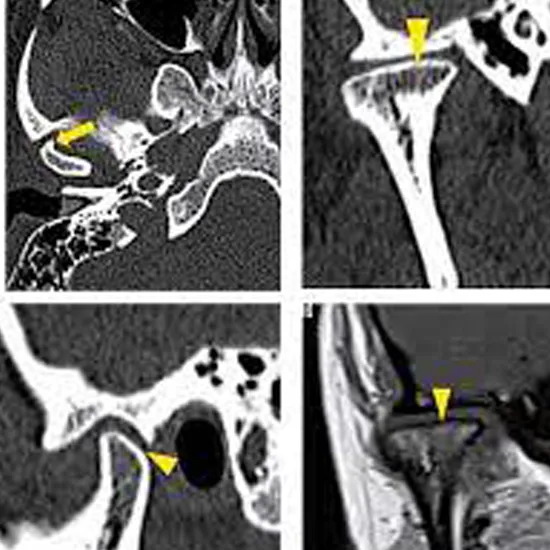

NCCT TM Joint is a plain study of the temporomandibular joint. It is a non-invasive imaging procedure used to diagnose the abnormalities related to the temporomandibular joints. These are two joints that connect the lower jaw to the skull.

NCCT TM Joint is an imaging diagnostic tool that uses X-rays with the computer to detect disorders and diseases related to the TM Joint and surrounding tissue. Patients should not avoid any abnormal symptoms related to TM joint disorders. They should go for screening to avoid any delay in diagnosis and treatment of the TM Joint.